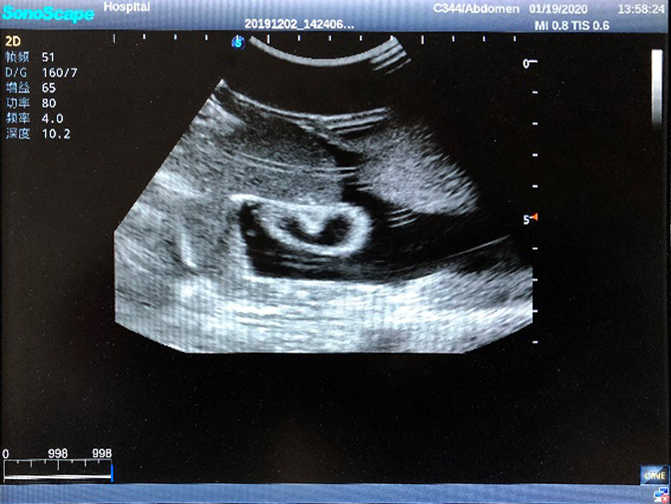

2)  High quality ultrasound image with clear structures like gallbladder, liver, intestines, arteries and veins etc.

3)  Compatible with all types of clinical ultrasound machines

4)  ltrasound gallbladder pathologies like cholecystitis, gallstone and polypoid degeneration

5)  Normal & pathological ultrasound live and intestine models inside